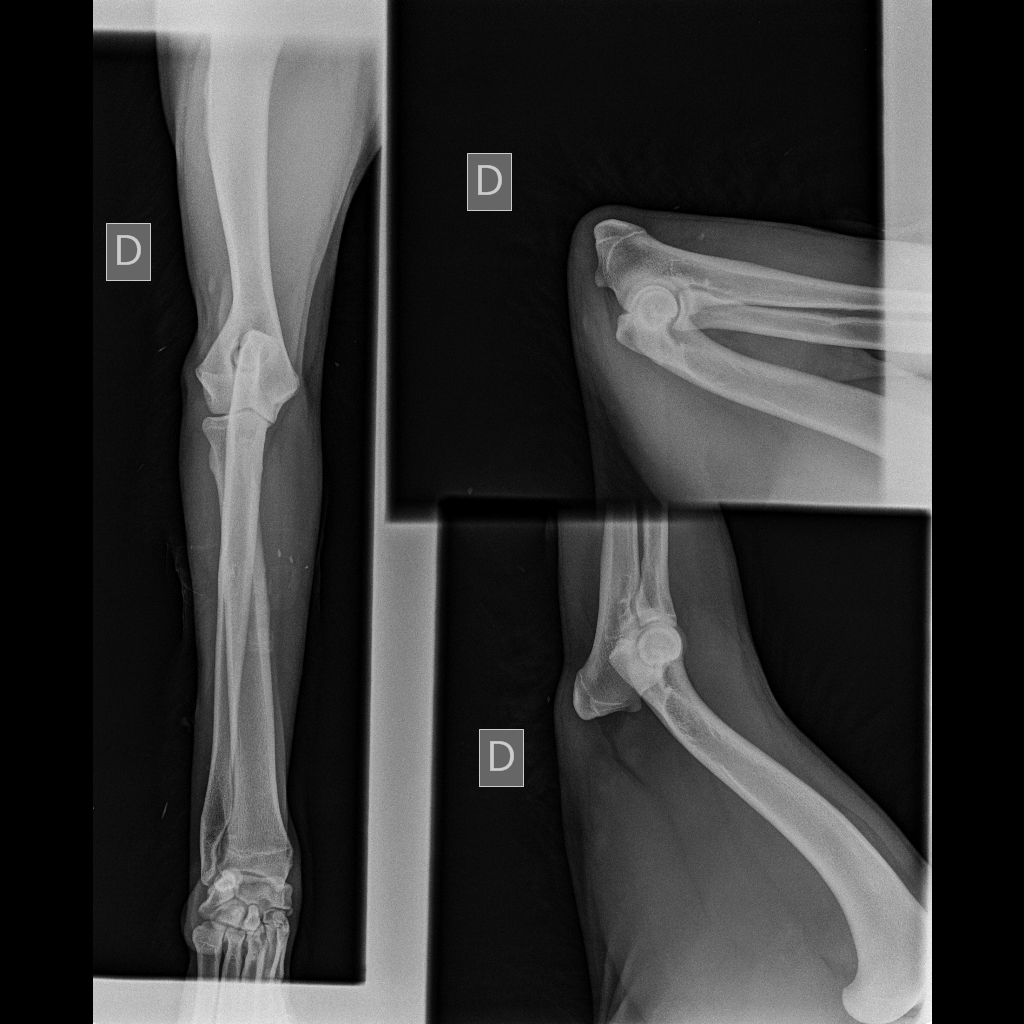

Télécharger radio eragone d'ainhoa coude

radio eragone d'ainhoa coude

radio des coudes de eragone

Télécharger radio eragone d'ainhoa coude 2

radio eragone d'ainhoa coude 2

radios des coudes de era